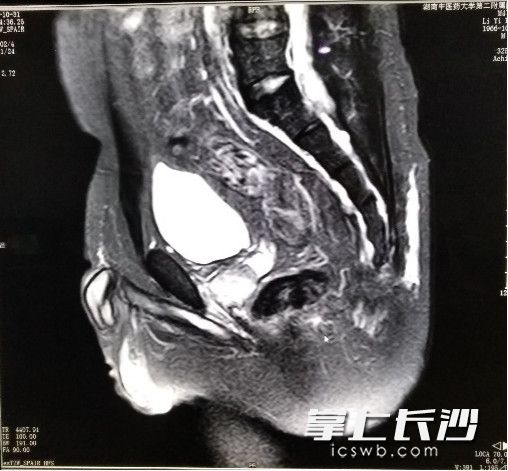

患者术前的核磁共振检查片

该科副主任医师莫黎全面细致地为李先生做了检查,最终被确诊为骶前囊肿。之前多次手术未能痊愈的关键,是未能完整切除囊壁组织,且反复手术导致周围组织粘连明显。核磁共振MRI检查结果显示,肿瘤较大,位置向上到达骶骨中段,后方及上方与骶前组织粘连明显,前面与直肠后壁紧密相贴。手术风险和难度都很高,不但要切除尾骨,还要切除部分骶骨,容易导致大出血,也可能损伤直肠而不得不做造瘘手术。